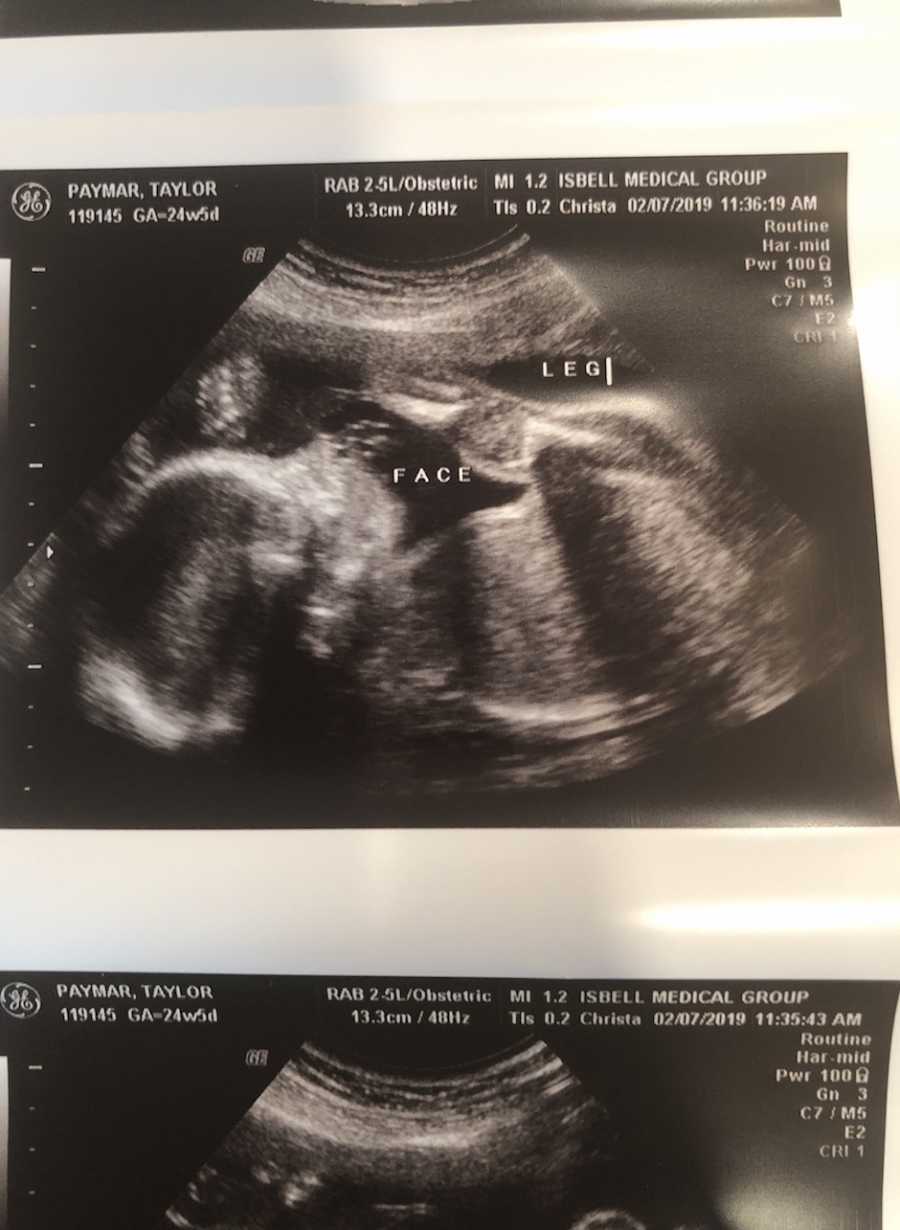

Brittle Bone Disease Pregnancy . oi may be detected as early as 14 weeks gestation but most is most commonly first noted at the time of routine anatomy fetal. osteogenesis imperfecta (oi) is a genetic disorder that prevents the body from building strong bones. pregnancy and osteogenesis imperfecta. This factsheet gives information about what to consider if you have oi and are planning. osteogenesis imperfecta (oi) is a rare genetic disorder characterized by defects in type i collagen that can pose serious complications. in pregnancies complicated by osteogenesis imperfecta, there is an increased risk to both the mother and. Some people have mild symptoms, like bones that break a little easier than normal. There are different types of oi, and the problems it causes vary. Others can have serious problems. the brittle bone disorders consortium of the national institute of health rare diseases clinical research network. brittle bone disease (osteogenesis imperfecta) is a genetic condition that causes bone weakness and fractures easily. Learn about the types, diagnosis, and life expectancy of this rare. That’s why it’s also called brittle bone disease.